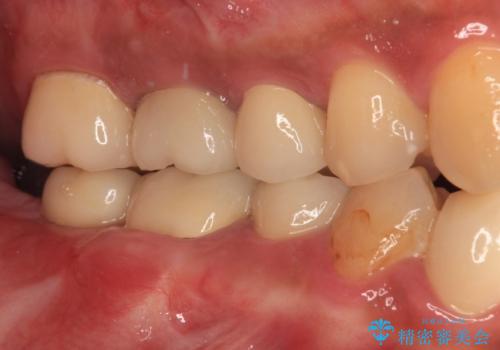

目立つ金属をすべてセラミックに 全顎的メタルフリー治療

小さい修復物の銀歯が装着されている歯はセラミックインレーにて、その他はオールセラミッククラウンにて補綴治療を進めることとしました。

矯正治療にも最初は興味を持たれていましたが、抜歯矯正の可能性が高いことや、治療期間、後戻り防止のためのマウスピース使用などが煩わしいと感じ、補綴治療のみを行うこととなりました。